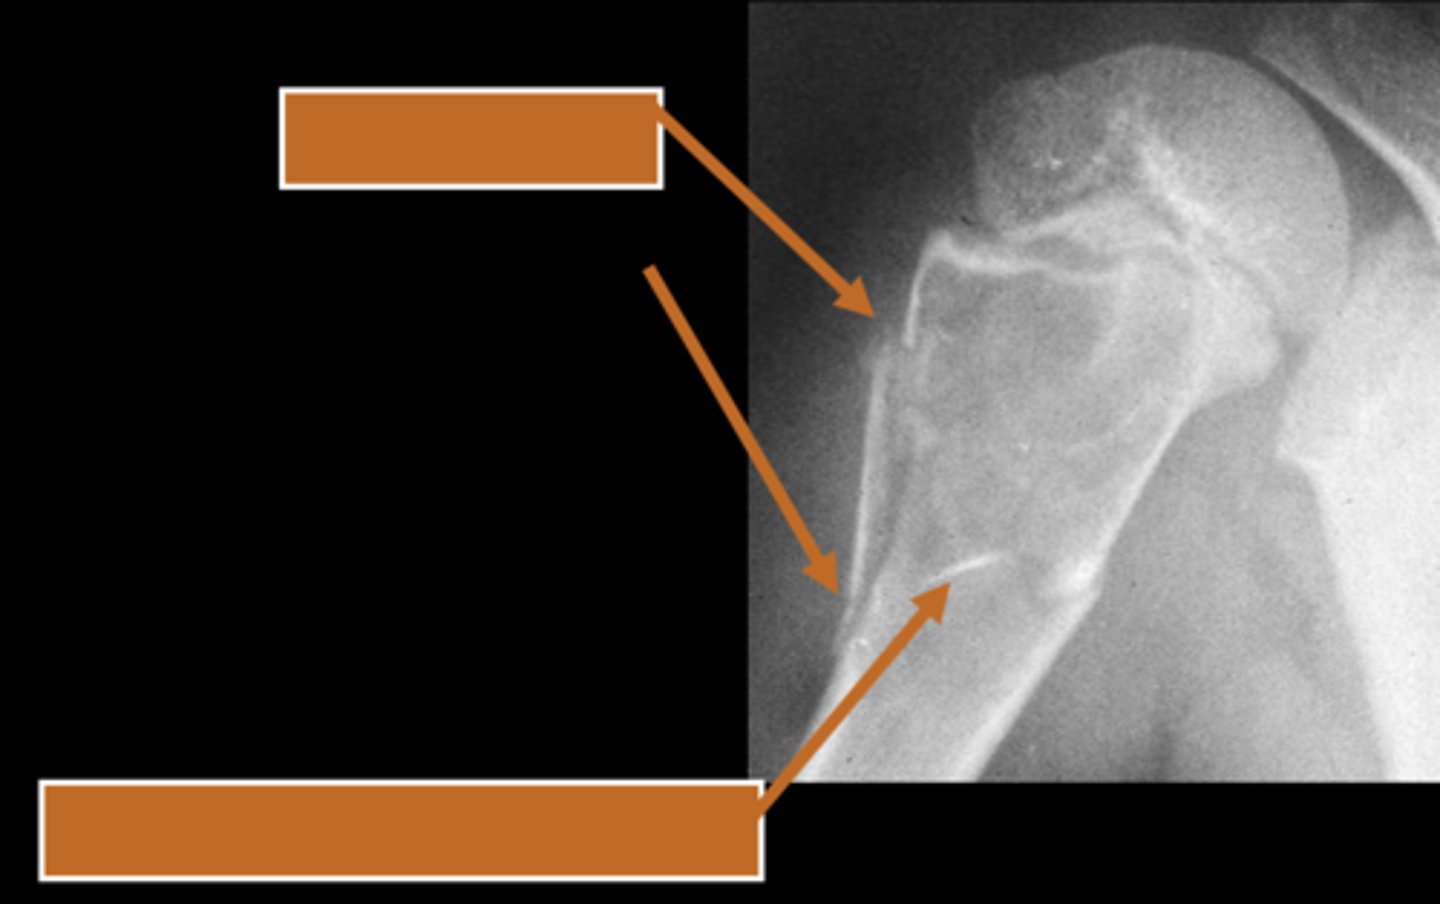

58

New cards

Geographic bone blister

ID radiographic feature of non-ossifying fibroma indicated by top arrow

<p>ID radiographic feature of non-ossifying fibroma indicated by top arrow</p>

59

Septations

ID radiographic feature of non-ossifying fibroma indicated by bottom arrow

<p>ID radiographic feature of non-ossifying fibroma indicated by bottom arrow</p>